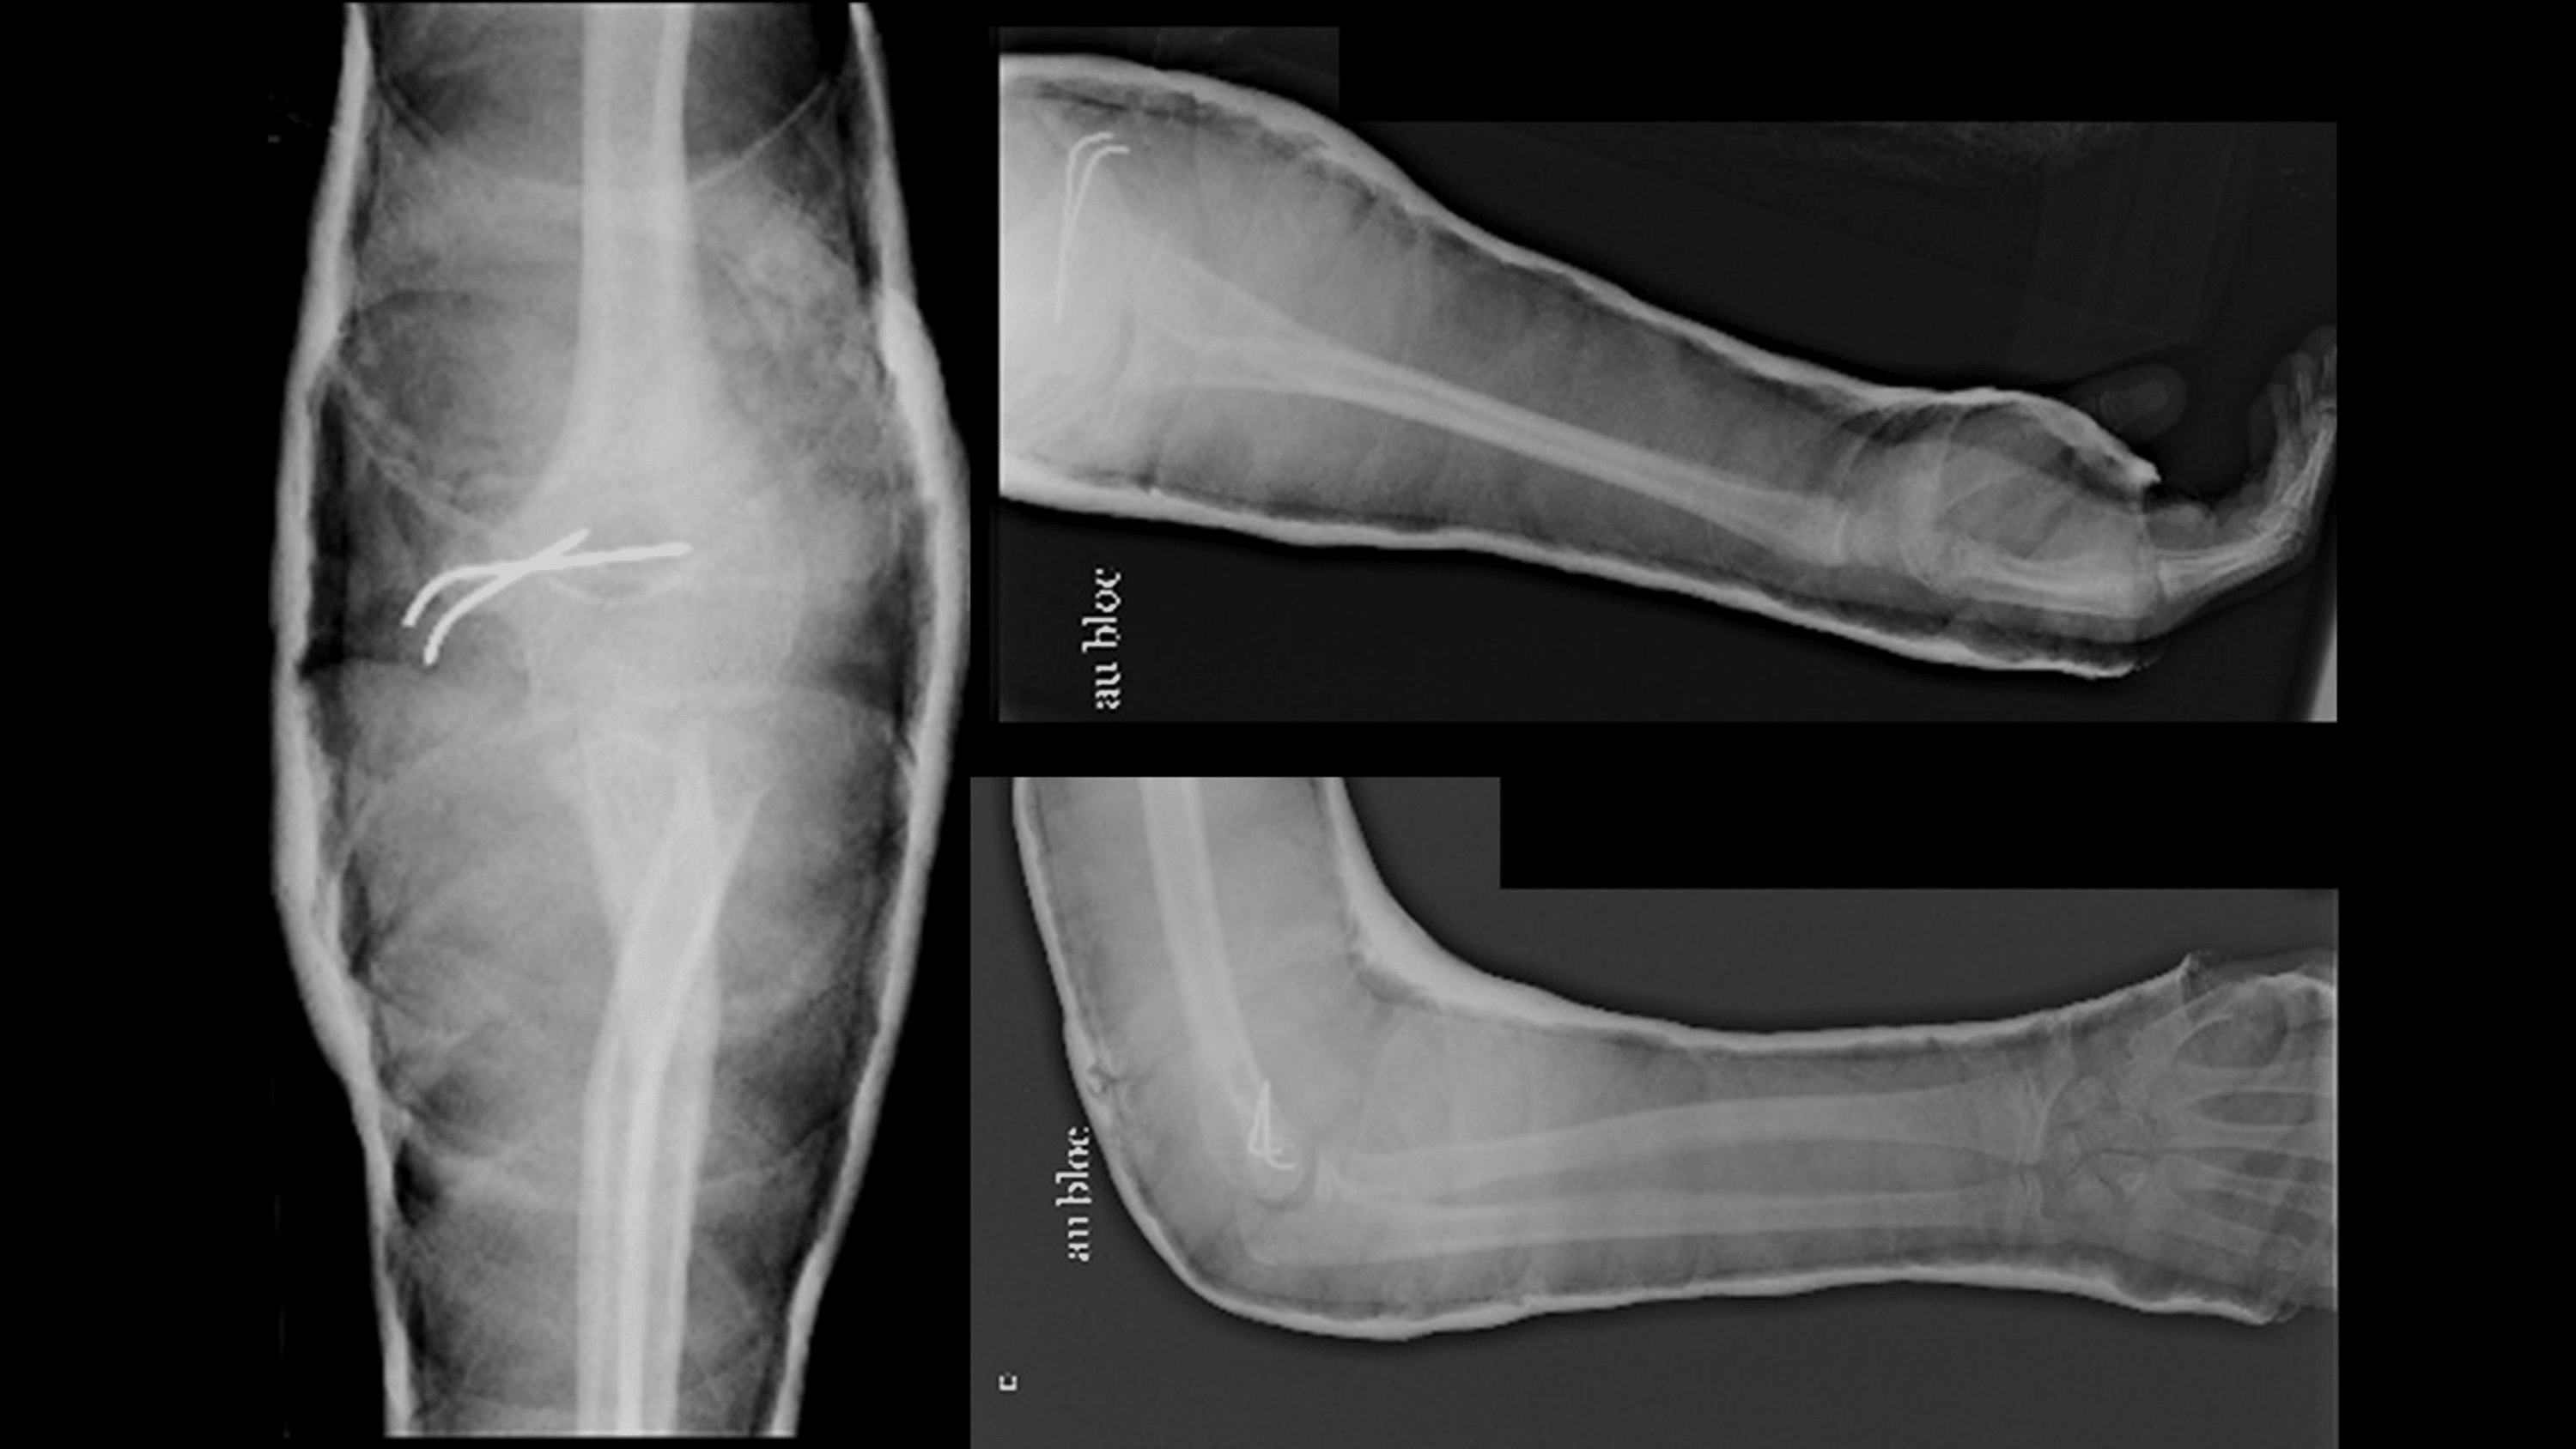

a, b Anteroposterior and lateral radiograph of a posterolateral elbow